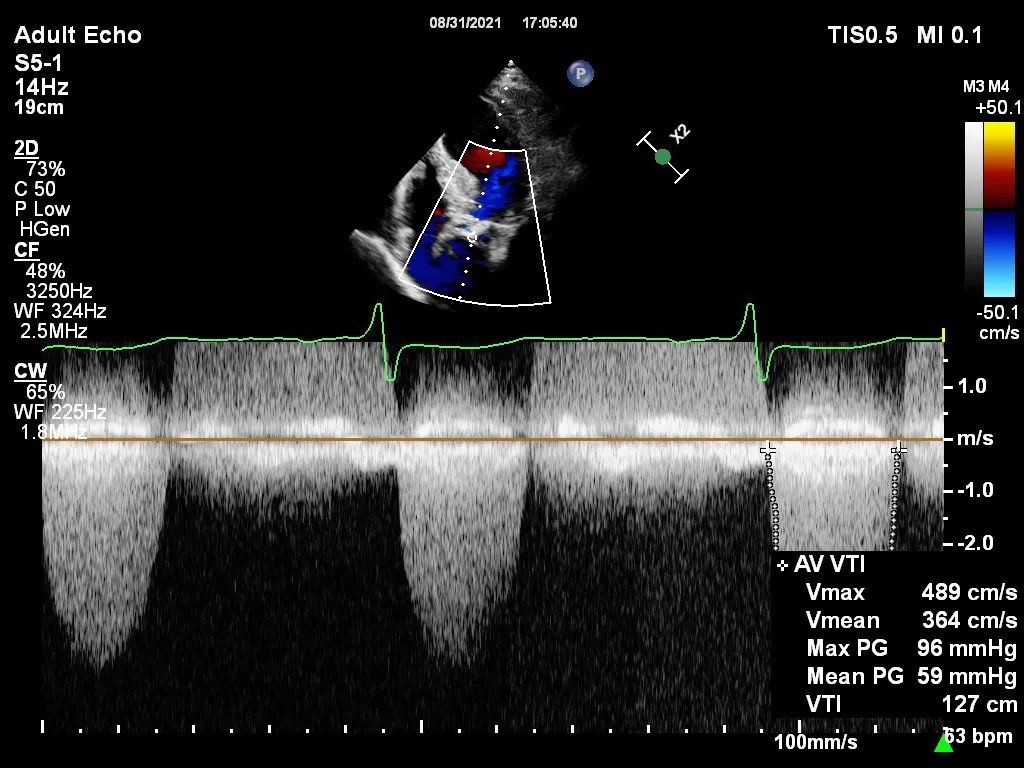

心脏彩超

峰值流速:5.0m/s

峰值跨瓣压差:100mmHg

平均跨瓣压差:61mmHg

左室射血分数EF值:0.28

左室舒张末期内径(LVD):5.6cm

主动脉瓣评估:左心扩大,主动脉瓣狭窄重度伴轻度反流

经过2个小时紧张有序的操作,手术取得圆满成功。术后即刻显示,瓣膜释放完毕后,患者的血流动力学状态明显好转,主动脉瓣前向血流速度降至1.6m/s,且瓣周漏近乎为零,达到了预期的治疗效果,患者苏醒后顺利从CCU转至普通病房。